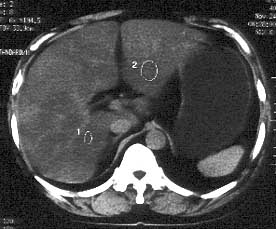

男性,53岁,腹痛、腹泻3天。体检:肝大,达肋下5cm,质中,无压痛。

ct平扫:肝脏密度普遍不均匀减低,ct值6-18hu,肝内血管相对显示为高密度。

ct诊断:脂肪肝。